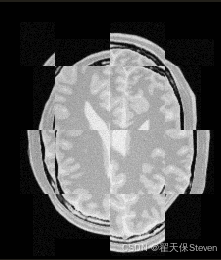

为直观对比配准效果,代码生成了配准前后的棋盘格图像:

- 配准前棋盘格:使用恒等变换(无对齐)生成,可见明显错位。

- 配准后棋盘格:使用最终变换生成,棋盘格线条连续,表明图像已对齐。

过程图像如下:

配准前棋盘格图

配准后棋盘格图